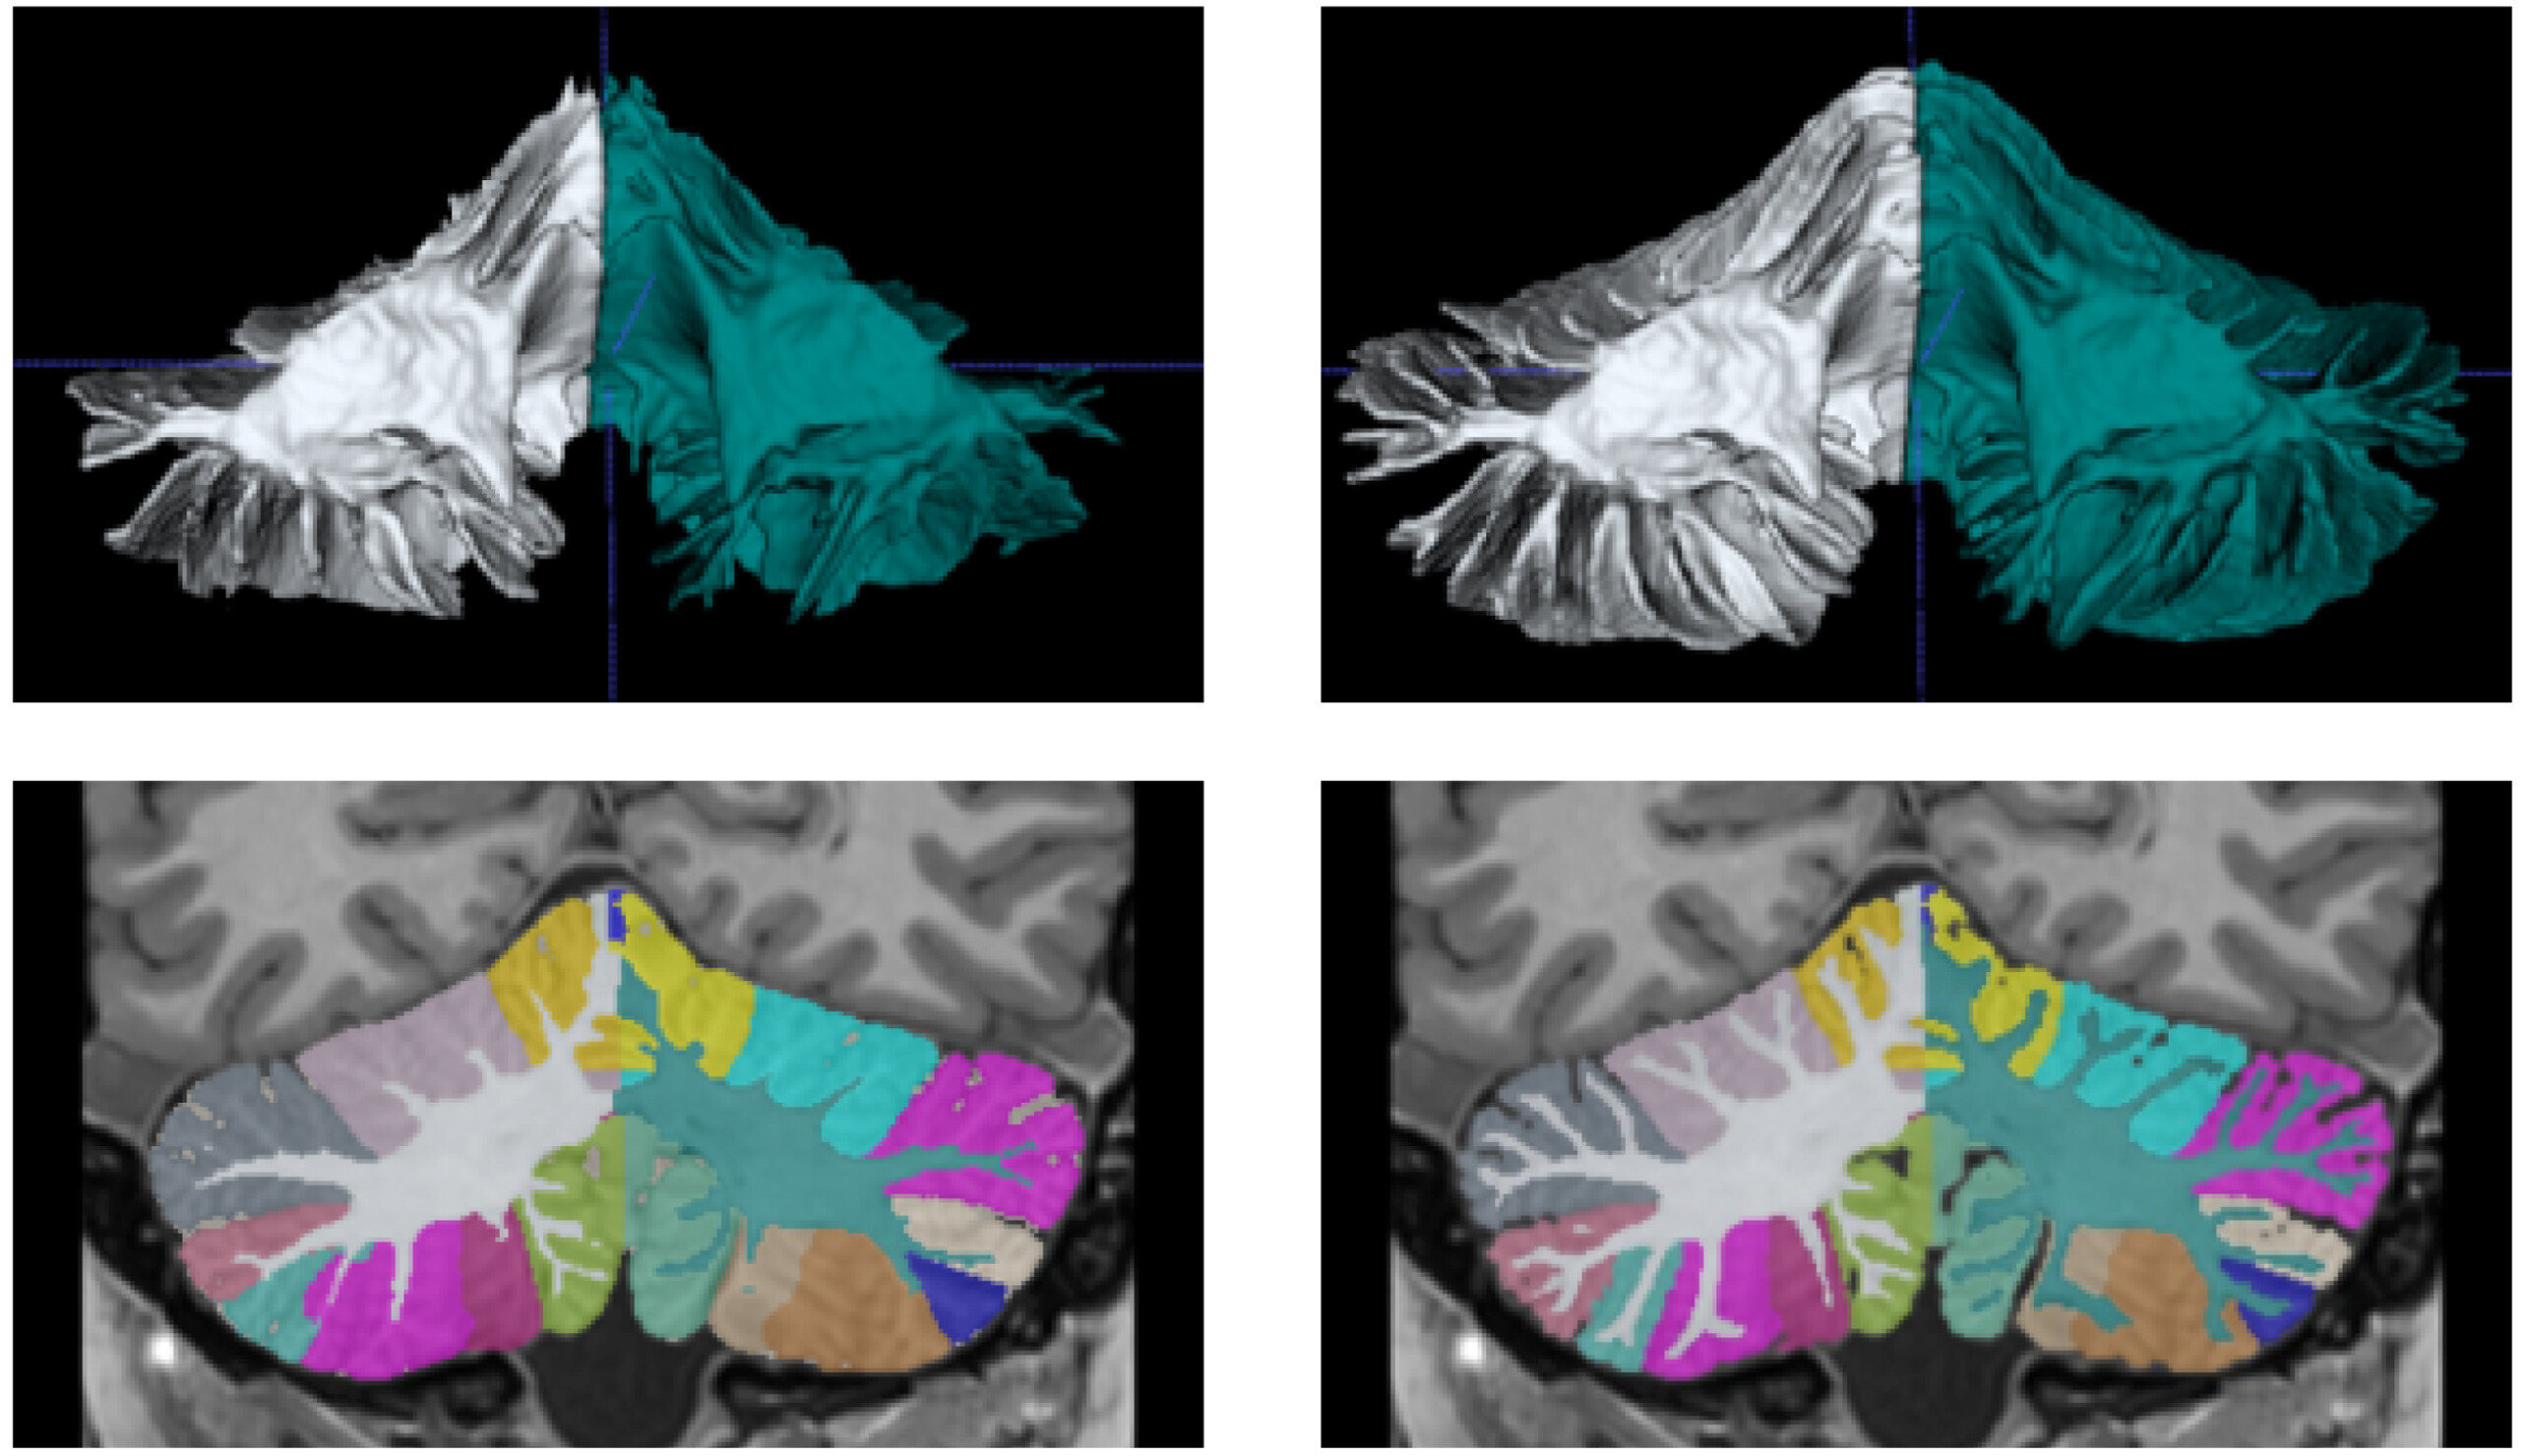

DeepCeres решает эту проблему, используя нейросети для преобразования стандартных снимков в сверхвысокое разрешение. Это позволяет исследователям и врачам получать детализированные изображения мозжечка без необходимости в дорогостоящем оборудовании.

Разработчики отмечают, что DeepCeres способен точно измерять 27 различных структур мозжечка. Это открывает новые возможности для диагностики и изучения неврологических и психиатрических заболеваний, а также помогает исследовать роль мозжечка в развитии нейродегенеративных патологий.